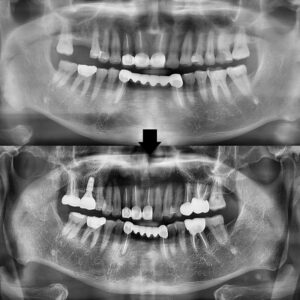

오늘은 저희 치과에 내원하신

환자분의 치료 과정을 공유드리려 합니다.

위 환자분께서는 처음 내원하실 때는

특별히 아프다기보다는 전체적으로

치료해야 할 곳들이 있어서 상담을

받아보고 싶다는 말씀을 하셨습니다.

검진 결과, 여러 부위에 걸쳐

치료가 필요한 상태였는데요.

우선 눈에 띄었던 것은 오른쪽 위 큰 어금니가

완전히 탈락된 상태였습니다.

해당 부위는 세마역임플란트 치료가 필요한 상황이었고,

그 주변의 다른 치아들 역시 상태가 좋지 않았습니다.

가장 우선적으로는 오른쪽 위 큰 어금니가

빠진 부위에 임플란트를 식립하였고,

세마역임플란트 식립 부위는 충분한 기간 동안

유착이 잘 이루어졌고 마지막으로 임플란트

최종 보철물을 장착하면서 치료를

모두 마무리할 수 있었습니다.